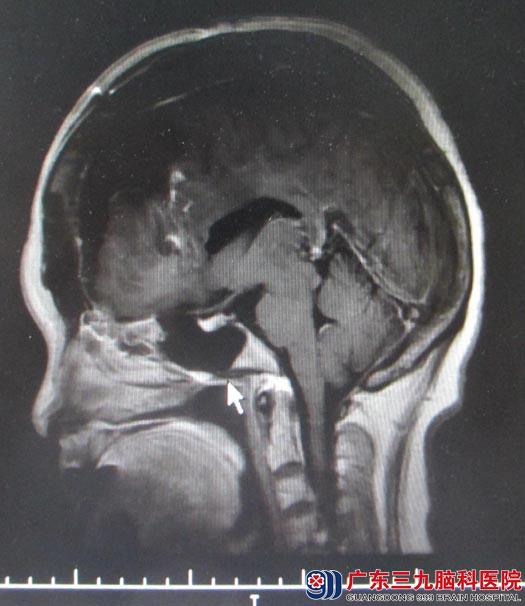

陈阿姨,52岁,二个月前开始出现头晕不适,当地医院考虑“高血压病”、“糖尿病”,给予对症治疗后头晕症状无明显好转。之后在一次爬山时,突然出现头晕加重,四肢乏力,遂行头颅CT检查提示:“前颅窝底巨大占位”。广东三九脑科医院头颅MR示“左额部、前颅窝巨大占位,大小约7cm×8cm,考虑脑膜瘤”,头颅CTA结果提示:1.左侧额部为主占位病变挤压双侧大脑前动脉向右偏移,同时双侧额极动脉为主增粗延长呈抱球状,参与病变供血;2.右侧椎动脉细小,以V4段明显;3.右侧胚胎型大脑后动脉;4.脑动脉粥样硬化改变,其中左侧大脑后动脉明显。

2015-04-02由鲁明主任主刀在全麻下行“左侧额部镰窦旁巨大脑膜瘤切除术”,术中见肿瘤主要位于左额部,与上矢状窦关系密切,侵犯大脑镰并推挤粘连下矢状窦,双侧大脑前动脉被肿瘤推压向右侧移位,显微镜下小心分离完好保护上矢状窦,分块切除肿瘤,部分大脑镰被肿瘤侵犯破坏,予电凝后切除,最终肿瘤镜下全切,手术顺利,术中出血600ml,输血400ml。患者术后恢复良好,无明显肢体运动及感觉障碍。